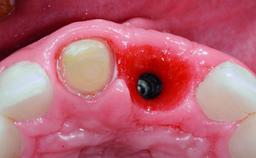

Replacement of a Compromised Upper Right Central Incisor: Hard- and Soft-tissue Augmentation, Late Placement of an RC Bone Level Implant

A 36-year-old male patient with a compromised maxillary central incisor was referred by his general dentist for consultation. The patient’s chief complaints were the gradual debonding of a temporary crown on the right central incisor and unsatisfactory esthetics due to an increasing diastema between the right central and lateral incisors. The patient reported a traumatic event some years previously, when a crown had been placed after root-canal treatment. The referring dentist wanted to provide a new crown restoration, but was concerned about the condition of the residual root. Anamnesis was negative for any other dental or periodontal pathology in the remaining dentition. The patient reported taking no medications: He was a smoker (10 to 15 cigs/day) and had realistic esthetic expectations.

Bone Volume Deficient horizontally, requiring prior grafting